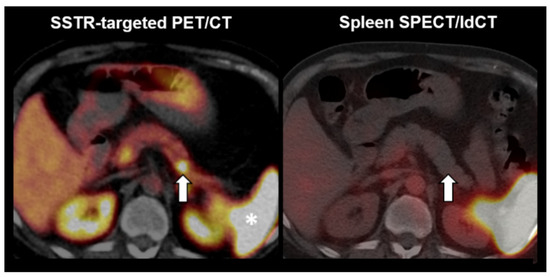

Figure 6 illustrates the case of a lesion rated as splenic tissue. A 63-year-old man with newly diagnosed esophageal adenocarcinoma presented with multiple unclear abdominal lesions. The patient had experienced traumatic rupture of the spleen several years before. 99mTc-labelled denatured red blood cells scintigraphy was performed (SPECT fused to low dose CT) in order to differentiate splenosis secondary to rupture of the spleen from potential lymph node metastases and peritoneal carcinomatosis secondary to the esophageal carcinoma. The lesions showed pronounced tracer uptake and, therefore, suggested splenic tissue (e.g., see perigastric lesion in the figure). Hence, after 3 neoadjuvant cycles of fluorouracil plus leucovorin, oxaliplatin, and docetaxel (FLOT) chemotherapy, a thoracoabdominal partial esophagectomy with total gastrectomy and locoregional lymphadenectomy was performed in curative intention. Histopathology showed no evidence of lymph node metastases or peritoneal carcinomatosis (ypT0, ypN0 (0/34), L0, V0, Pn0, UICC-Stadium 0, locally R0). Using the quantitative reading in selective spleen scintigraphy, the lesion would have been correctly classified (higher lesional uptake ratio than the cutoff, i.e., 1.22 > 0.75).

Figure 6.

Example of a positive reading in spleen scintigraphy. Left anterior perigastric lesion. (Left) 99mTc-labelled denatured red blood cells SPECT. (Middle) 99mTc-labelled denatured red blood cells SPECT fused to low dose CT. (Right) low dose CT.